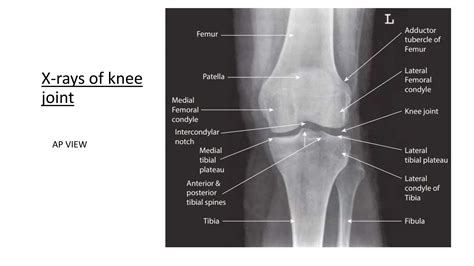

• Femur (Thigh Bone): The large, upper bone of the leg. Its lower end features two rounded projections called condyles, which roll and glide on the top of the shinbone.

• Tibia (Shinbone): The primary weight-bearing bone of the lower leg. The upper surface of the tibia, known as the tibial plateau, provides the base upon which the femur rests.

• Patella (Kneecap): A triangular-shaped sesamoid bone that sits in front of the knee joint. It is embedded within the quadriceps tendon and acts as a pulley system, increasing the mechanical leverage of the thigh muscles.

Articular cartilage is the tough, smooth tissue that covers the ends of the femur and the top of the tibia. This slippery surface allows the bones to glide over one another with minimal friction. Deep to this, we find the meniscus—two C-shaped pads of fibrocartilage located between the femur and tibia. The medial meniscus and the lateral meniscus act as shock absorbers, dispersing the weight of the body across the joint and providing stability.